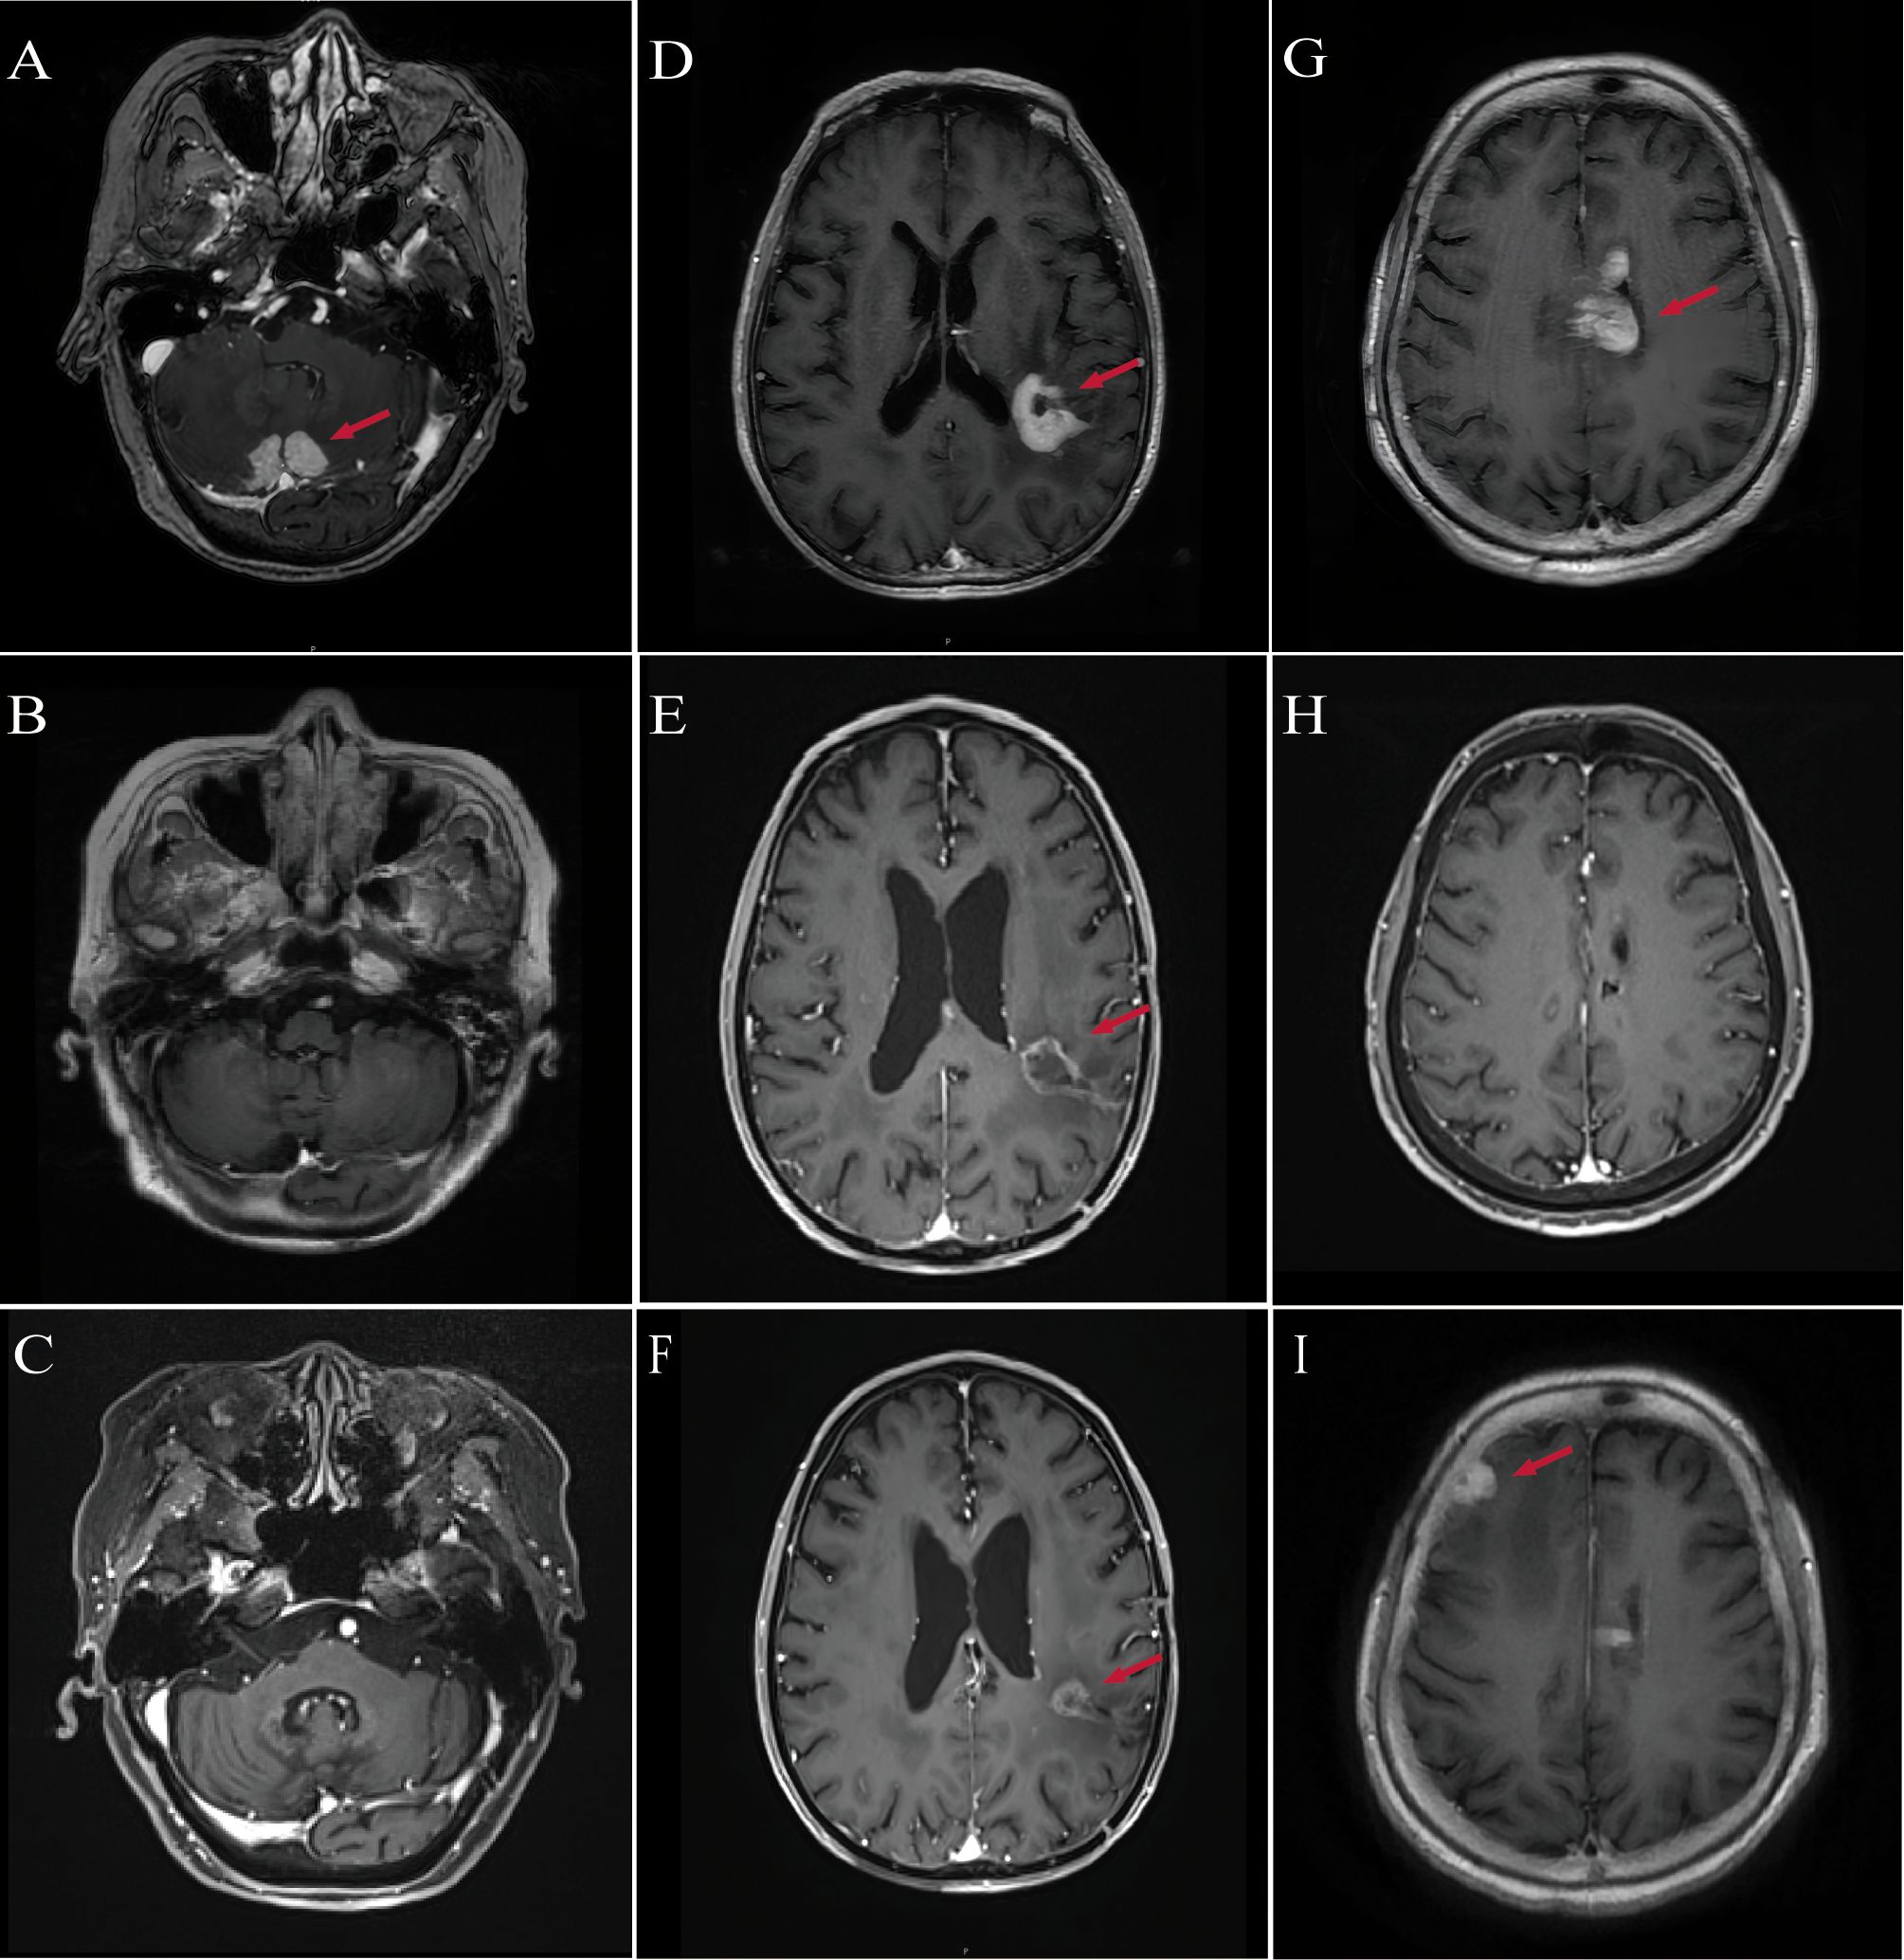

Contrast-enhanced brain MRI demonstrated multiple hyperintense lesions in the bilateral cerebellar hemispheres, leptomeninges, and cerebellar tentorium, suspicious for PCNSL (Figure 1A). Stereotactic brain biopsy on February 26, 2023 confirmed DLBCL, non-germinal center B-cell (non-GCB) subtype. Positron emission tomography–CT (PET/CT) and bone marrow biopsy excluded systemic involvement. The International Extranodal Lymphoma Study Group (IELSG) score was 3, indicating intermediate risk.

Figure 1. MRI imaging of patients diagnosed with PCNSL. (A) Patient #1: Baseline contrast-enhanced MRI shows bilateral cerebellar lesions (red arrows), consistent with PCNSL. (B) Patient #1: Follow-up MRI at 3 months post-treatment shows complete resolution of cerebellar lesions. (C) Patient #1: MRI at 29 months post-treatment confirms sustained complete remission. (D) Patient #2: Baseline MRI reveals enhancing lesions in the left parietal lobe, midbrain, and thalamus (red arrows). (E) Patient #2: MRI at 3 months post-treatment reveals a 40% reduction in tumor size compared with baseline. (F) Patient #2: MRI at 7 months post-treatment shows approximately 50% reduction in lesion diameter relative to baseline. (G) Patient #3: Baseline MRI reveals multifocal lesions involving the periventricular areas, lateral ventricles, fourth ventricular ependyma, and corpus callosum (red arrows). (H) Patient #3: MRI at 3 months post-treatment shows near-complete remission of previously noted lesions. (I) Patient #3: MRI at 10 months post-treatment reveals recurrent enhancing lesions in the right frontotemporal region and basal ganglia.

Follow-up MRI in March 2023 demonstrated PR, and by June 2023, CR was achieved (Figure 1B). Neurological function significantly improved, with ECOG performance status improved to 3 and MMSE increasing to 20, indicating mild-to-moderate cognitive impairment. In January 2024, she sustained multiple fractures from a fall, resulting in reduced mobility, but continued on orelabrutinib therapy. As of the most recent follow-up in August 2025, she remains in CR without evidence of disease recurrence (Figure 1C).

Contrast-enhanced MRI revealed abnormal enhancement in the left parietal lobe, midbrain, and thalamus (Figure 1D). On February 28, 2024, the patient underwent neuro-navigation-guided tumor resection. Postoperatively, he developed aphasia, dysphagia, and right-sided hemiplegia. His functional status deteriorated to ECOG 4, while cognitive function remained MMSE 20. Histopathology confirmed non-GCB DLBCL. PET/CT and bone marrow biopsy excluded systemic involvement. The IELSG score was 2, indicating intermediate risk.

MRI in June 2024 demonstrated marked reduction of the intracranial lesions and decreased enhancement around the resection cavity. Clinically, neurological function improved, including memory, speech, and right-sided limb strength. Functional status recovered to ECOG 2, and MMSE improved to 22. Radiological assessment showed PR (Figure 1E). As of the latest follow-up in October 2024, the patient remains in PR (Figure 1F).

Contrast-enhanced brain MRI demonstrated multiple abnormal lesions near the bilateral lateral ventricles, fourth ventricle ependyma, and corpus callosum (Figure 1G). Cerebrospinal fluid analysis showed elevated protein (2+). Stereotactic brain biopsy on September 11, 2024 confirmed non-GCB DLBCL. PET/CT and bone marrow biopsy excluded systemic involvement. The IELSG score was 4, indicating high-risk disease. Postoperatively, the patient developed severe pneumonia, which further compromised her general condition.

Given her postoperative pneumonia, multiple comorbidities, and poor performance status, the patient was considered ineligible for HD-MTX–based chemotherapy. Following multidisciplinary team discussion, she received induction therapy in the Hematology Department consisting of rituximab (500 mg) combined with oral orelabrutinib (150 mg daily), achieving CR after four cycles (Figure 1H). On December 5, 2024, she was transferred to the Oncology Department and underwent rd-WBRT (23.5 Gy in 13 fractions) while continuing oral orelabrutinib. Follow-up MRI in March 2025 showed sustained CR, accompanied by improvement in neurological function, with ECOG performance status improving from 4 to 3 and MMSE score increasing from 15 to 18.

However, due to the high financial cost of orelabrutinib, treatment was modified on March 18, 2025 to lenalidomide (10 mg daily) plus rituximab. At the subsequent follow-up on July 1, 2025, MRI demonstrated disease progression (Figure 1I). Consequently, the regimen was adjusted to rituximab (500 mg) combined with oral orelabrutinib (150 mg daily) for maintenance therapy. As of the latest follow-up, her performance and cognitive status have remained stable, and repeat imaging is pending.